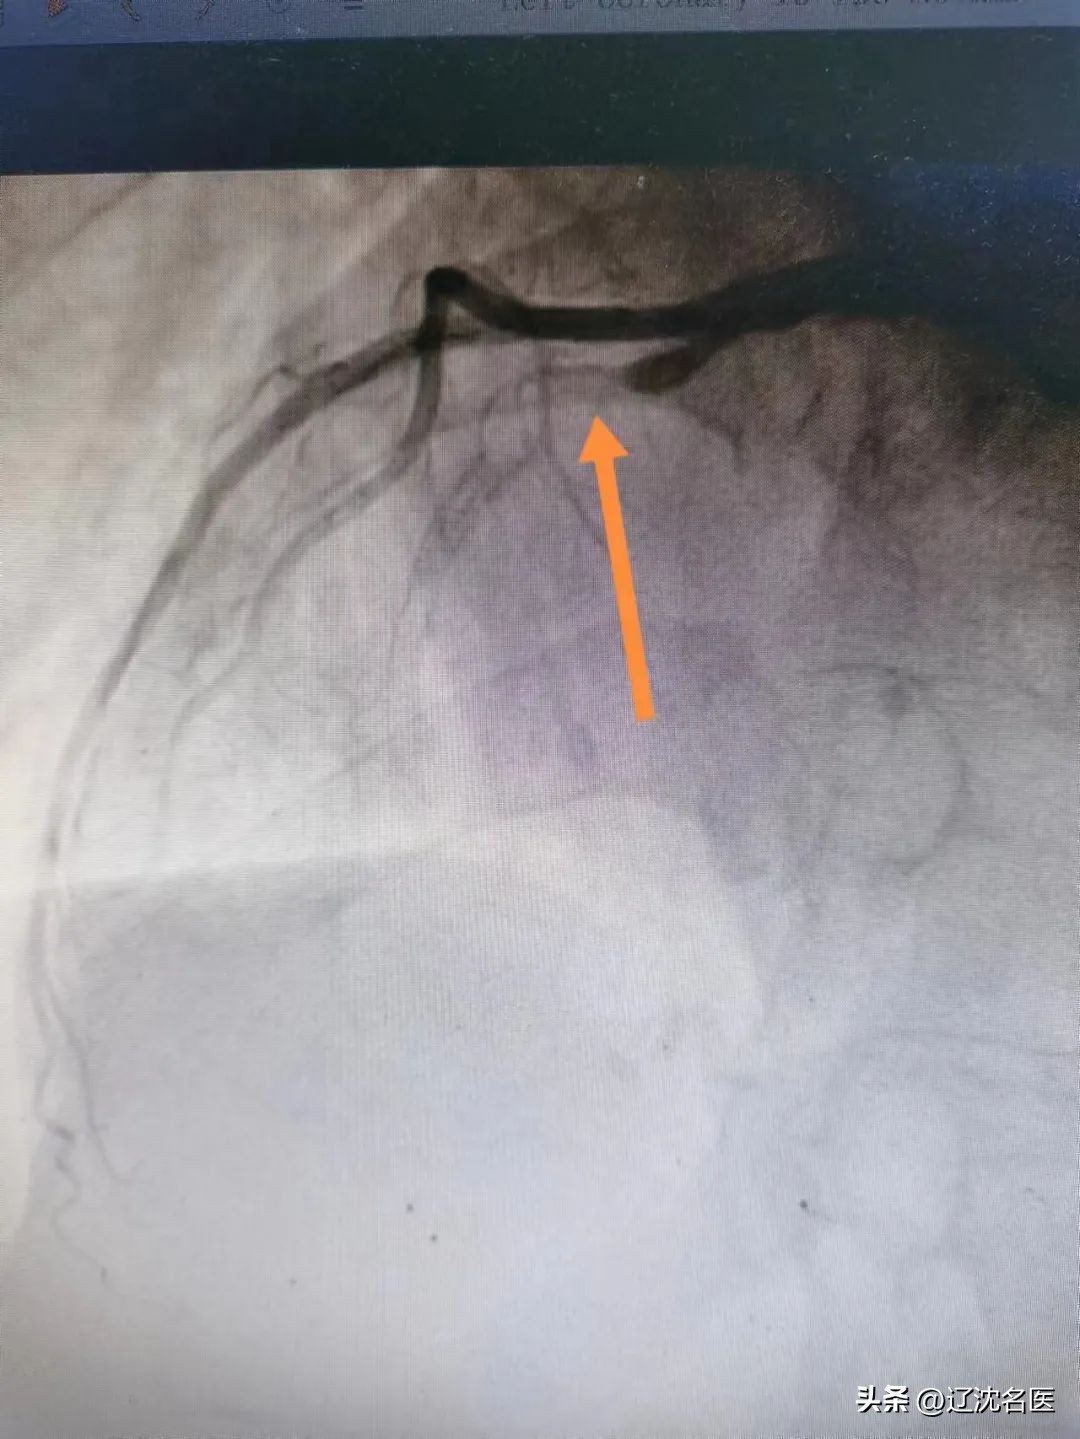

由于患者特殊的生理结构,左冠状动脉位于心脏右侧,右冠状动脉位于心脏左侧,冠状动脉造影时,X线投照体位选择,导管送入冠脉开口的旋转动作应与一般患者的常规操作相反。加之,右位心易合并其他心脏畸形,或发生血管变异和走行异常 。

15时34分,患者被推入导管室,虽然已经做了术前评估和心理准备,但一到实操,大家还是如履薄冰。在佟主任带领下,团队充分发挥协作精神,改变惯有思维,谨慎操作。冠脉造影示:主要血管LAD开口90%狭窄,狭窄后100%闭塞,佟主任经慎重考量,经冠脉内溶栓及血栓抽吸,最后在LAD中远端置入支架一枚,血管顺利开通,TIMI血流3级,患者转危为安,大家如释重负。